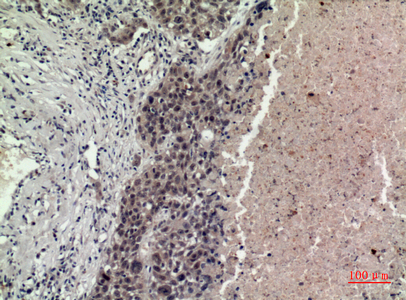

| IHC | 1/50-1/100 |